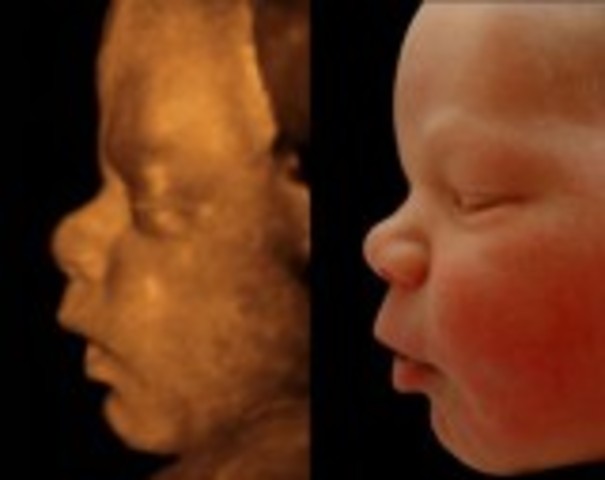

week8

1.Starts to practice moving (not felt by mom till week 20)

2.The face is beginning to take shape

3.first prenatal visit

• week9

week9

1.The embryo has grown to 1.2 inches

2.The eyelids are developed, although they stay closed for several months

3.the brain is growing very rapidly

• week10

week10

1.the embryo is now called a fetus

2.The fetus is now the size of a small strawberry

3.The ears and nose can now be seen clearly